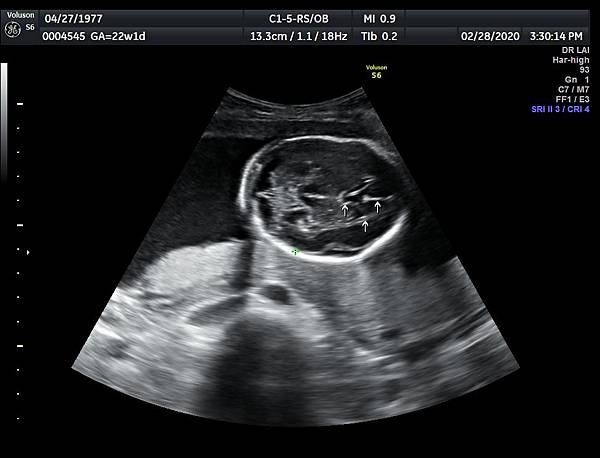

2016年8月4日在執行胎兒高層次超音波檢查時,我發現胎兒腦部的CSP(cavum septum pellucidum)很不清楚(附圖1~4),遇到這種情況,需要仔細評估胎兒腦部的駢胝體,因為CSP的天花板是駢胝體,CSP不明顯時,要合理的懷疑駢胝體沒有發育,或駢胝體下方有長東西(例如lipoma),駢胝體是連接左右大腦的神經纖維所組成。

1. 矢狀切面(sagittal plane):駢胝體呈現類似三明治的中間黑色部分,上面一層薄薄白色的區域是callosum sulcus,打上flow可以看到pericallosum artery在駢胝體上面的周圍,pericallosum artery來源是前腦動脈,參考附圖 6~10,三明治下面白白的部分是和CSP做比較得到的,如果這一層長lipoma(附圖 5),CSP很可能看不到。

3. 要看完整的駢胝體,我的經驗是胎頭臉朝上比臉朝下好。(附圖 11~14)